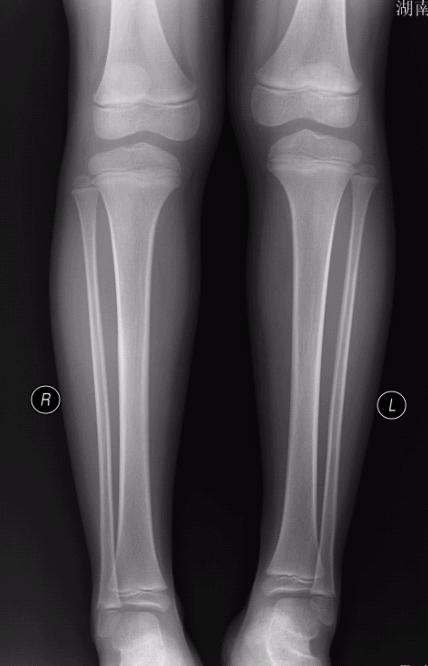

左胫骨中段前缘局限性骨皮质增厚,其内隐约见一低密度影,考虑骨样骨瘤可能,局限性骨皮质增厚可能,建议ct进一步检查。最后一张片子应该是l吧。

左胫骨前缘骨皮质增厚,有向前凸起改变,与之比较右侧胫骨皮质均匀光整。支持二楼的意见。从骨性标记看,小腿的左右标注楼主有误。

左胫骨中段前缘局限性骨皮质增厚。